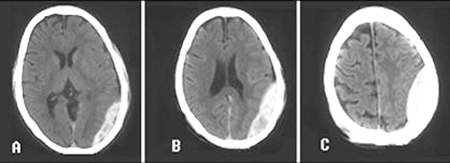

- head CT (non-contrast):

characteristically crescent-shaped; blood does not cross the midline; in the setting of acute bleeding, areas of hypodense and hyperdense haematoma produce a swirling appearance

a hyperdense extra-axial lesion with smooth margins on CT; a lentiform appearance, forming a biconvex shape as blood pushes on the brain surface; blood does not cross suture lines; swirling areas of varying density indicates active bleeding